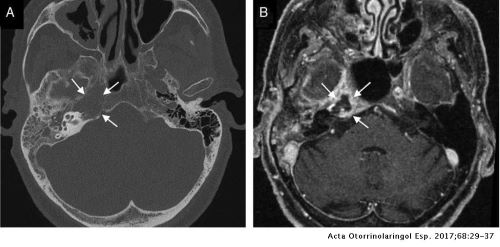

Se realizó una tomografía computarizada de cráneo con énfasis en fosa posterior y mastoides (Figura 1). Ante los hallazgos clínicos y paraclínicos se diagnostica 1) infección de sistema nervioso central: meningitis bacteriana. 2) otitis media supurativa derecha complicada con absceso y mastoiditis severa. 3) Síndrome de Gradenigo. Por lo cual se mantuvo antibioticoterapia de amplio espectro con Imipenem y Vancomicina. Al 3er día de estancia intrahospitalaria fue valorado por el servicio de neurocirugía para probable manejo quirúrgico.

Aunque el diagnóstico de este síndrome es clínico, los estudios de imagen permiten objetivar la patología siendo el de elección la tomografía computada (TC) de alta resolución con contraste del oído interno y de la base del cráneo que permite evaluar el hueso temporal y el peñasco, así como de la mastoides. Otros métodos útiles son la resonancia magnética (RM) y el gammagrama óseo6. En este sentido, la RM es superior al TC en el hallazgo de complicaciones intracraneales con una sensibilidad del 95% y una especificidad de 86% en la detección del trombo en la trombosis séptica del seno cavernoso secundaria a petrositis aguda2. El diagnóstico diferencial incluye: tumores como meningiomas, sarcomas o neurinomas y aneurismas7. En el caso clínico, la TC nos brindó la información complementaria suficiente para confirmar el diagnóstico, además de la falta de disponibilidad inmediata de la RM.